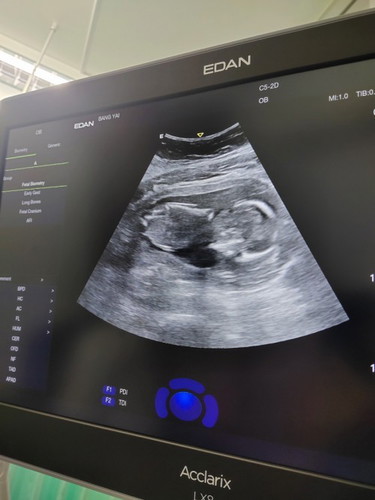

วันนี้ได้ไปฝากครรมาค่ะ เพิ่งไปฝาก อายุครรภ์ ประมาน 16+4 ถ้านับจากประจำเดือนที่ขาด แต่ตอนคุณหมอซาว คุณหมอบอกว่า เด็กโตกว่าประจำเดือน (ถ้าฟังไม่ผิด นะคะ) ก็อยู่ที่ครรภ์ 17 สัปดาห์ ตรวจมาก็เสี่ยงเป็นความดันโลหิตสูง เสี่ยงภาวะครรภ์เป็นพิษ ก็แอบตกใจนะคะ แต่ก็จะพยายาม ลด หวาน มัน เค็ม ตามที่คุณหมอบอก เรากับแฟน ไม่ได้อยู่ด้วยกันค่ะ แฟนก็ไม่ค่อยสนใจ เราคิดว่าเขาจะดีใจที่ได้เห็น วิดีโอตอนซาว ที่เราส่งให้ดู แต่ดูเหมือนว่า เขาไม่ได้ตื่นเต้นหรือดีใจเลย ผิดกับคู่อื่น ที่เขาสนใจ ดูแลกันดี หาอะไรบำรุงให้ลูกให้เมียทาน แต่แฟนเราป่าวเลย เราควรทำไงดีคะ แค่แชร์ประสบการ และอยากได้กำลังใจ (งดดราม่านะคะ) #ขอบคุณสำหรับคำตอบค่ะ